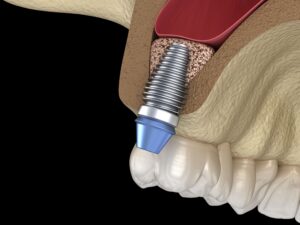

When fully set in vivo,OSSPORE BONE FILLER is drill able and can be used to for attachments.

Compatibility with Autograft, allograft, hardware